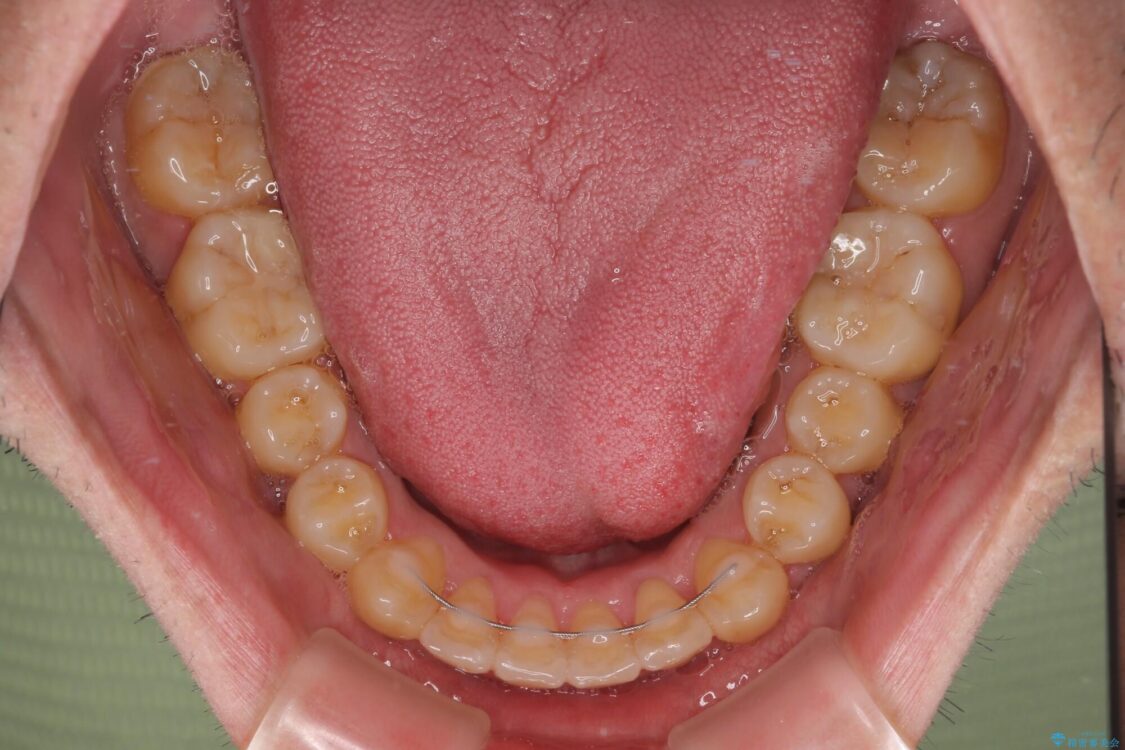

八重歯と前歯のクロスバイトを改善したいとのことで来院された患者様です。

デコボコの程度は強かったのですが、口元の突出感はなかったため、非抜歯矯正としました。

治療前

• 八重歯とクロスバイト 目立たないワイヤー装置で矯正治療 治療前画像